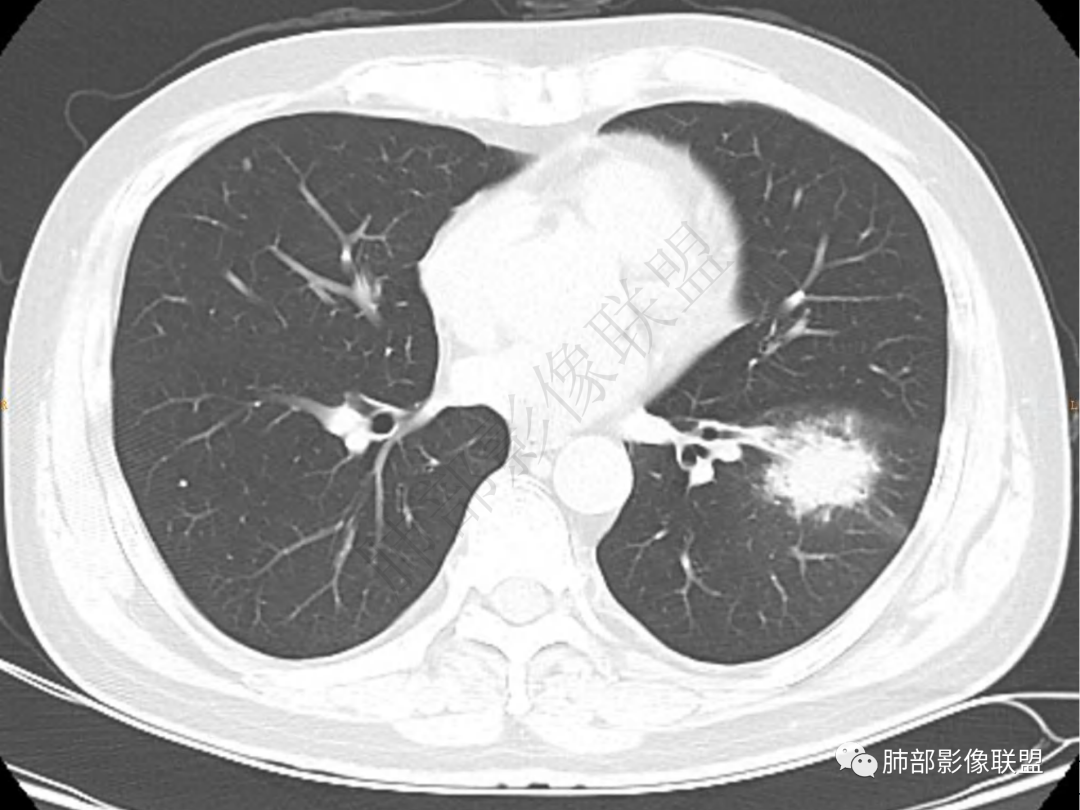

4.实性部分不均匀环形强化并显示一小范围低密度坏死区或空洞。较之肺窗,整体纵隔窗范围较小,提示病灶并不十分密实。抑或为不同时段图像。

1.病灶不够密实,没有典型分叶,收缩乏力等,支气管未见截断等,缺乏一般肿瘤性肿块特征。

2.周围磨玻璃影边界不清缺乏限制,甚至“激惹”到相邻肺叶,也许提示较明显的炎性水肿。

正如多数老师分析到的,本例病灶炎性特点比较明显。

肺脓肿:可宽基底与胸膜相连,附近胸膜增厚——炎性特点

肺脓肿:边界模糊不清,或者块影为类圆形,无明显分叶,边缘平直为主,刀切征——炎性特点三、病灶周围特点:肺脓肿:病灶非远端有片状GGO——炎性特点四、近端支气管阻塞:肺脓肿:常有引流支气管伴管壁增厚或者支气管沿洞壁走行。五:坏死壁:肺脓肿:大多壁厚,少数壁薄,没有壁结节,内壁清楚光整——炎性特点

肺脓肿:环形强化,强化较显著。如出现明显囊壁样强化甚至边缘“憩室”样突出,高度支持肺脓肿。